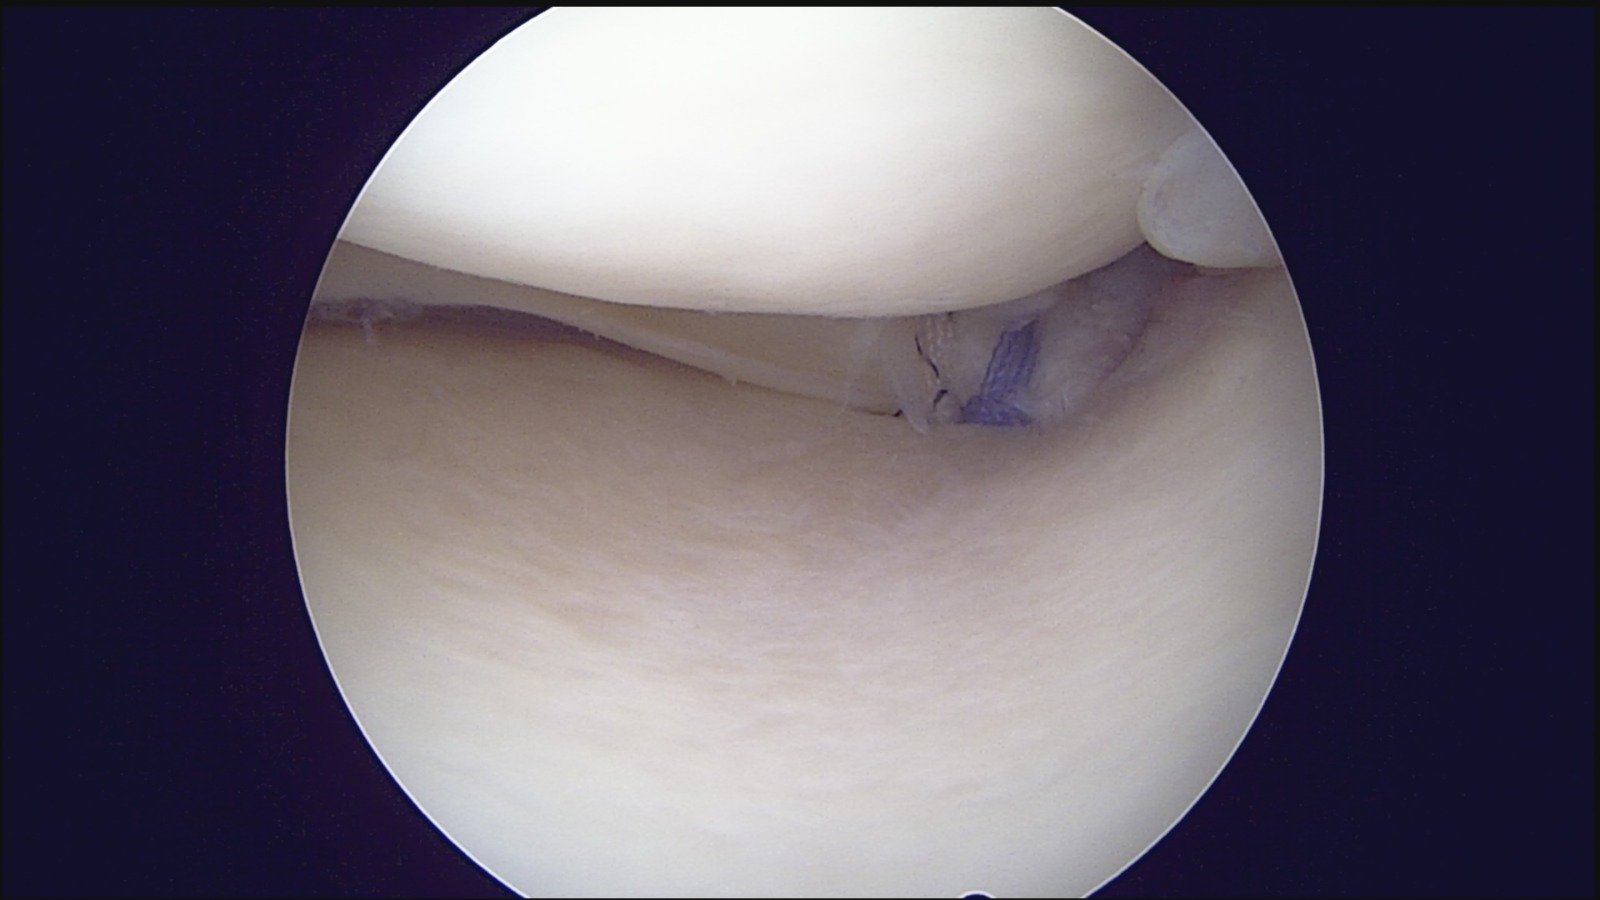

GalleryShoulder rotator cuff repair Meniscus root repair Meniscus repair Bankart repair for recurrent shoulder dislocation ACL reconstruction Machines Instruments